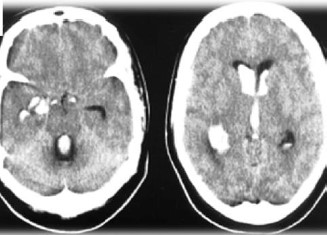

Paciente feminina, 60 anos, levada ao PS por cefaleia súbita, seguida de sonolência, confusão mental e hemiplegia esquerda. A Tomografia foi realizada e apresentou os seguintes achados:

Sobre o caso descrito, assinale a alternativa CORRETA: